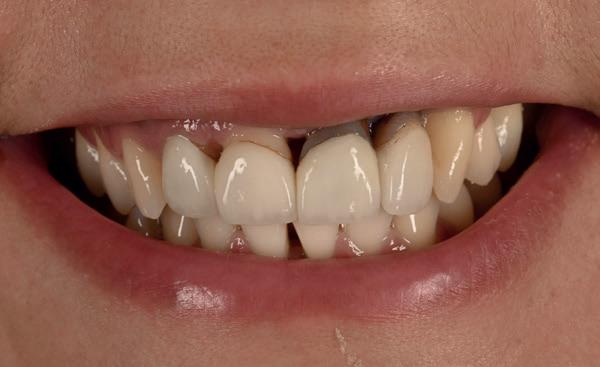

Ook de rol van de patiënt is hierin van doorslaggevend belang. In dit geval toonde de patiënt een hoge mate van motivatie en betrokkenheid. Hij verbeterde zijn mondhygiëne aanzienlijk en bleef gedurende het gehele behandeltraject therapietrouw en besluitvaardig. Zonder deze actieve medewerking was het bereikte resultaat niet mogelijk geweest. Het eindresultaat leidde tot merkbare tevredenheid bij de patiënt, die na afronding van de behandeling aangaf zich zichtbaar en voelbaar tien jaar jonger

te voelen (afbeelding 18) Een uitspraak die treffend weerspiegelt wat bereikt kan worden wanneer visie, interdisciplinaire samenwerking en patiëntbetrokkenheid samenkomen.

18. Studiofoto na afbehandeling